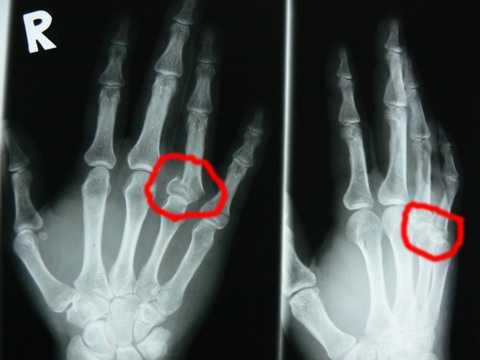

現地のガイドさんに近くの病院に連れて行ってもらい、レントゲンを撮って見てみると見事に折れてます。小指もちょっと逆方向に曲がっている。(みんな引かないでー)

指輪をしていたので、すぐに外し、すぐに病院に連れてかれてレントゲンを撮りました。恐る恐る写真を見るとうわーっ。やってしまった。どんどん手が腫れてくるし、しびれてる。

骨折!足跡記録に「箸が握れるようになりました。」とあったのでビックリしました。しかしキレイに折れていて幸いでしたネ。またこのレントゲン写真は、キレイな指骨を実にキレイに撮影していますネ(-_-;)。

確かに、きれいに折れてずれてます。

折れたときは、薬指が中指の方に80度くらいまがってましたが、

やばいと思ってまっすぐに自分で戻したんです。